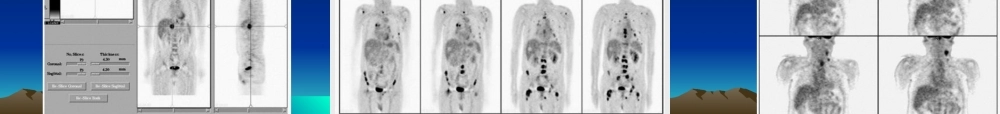

【病史】男,43岁,咳嗽、咳痰半年余,无咯血及体重下降【病史】男,56岁。CT发现颅病例12【病史】男,28岁,头痛、性格改变约半年,MR示右额叶T2信号增高。病例15(fànɡliáo)后1年。病例40【病史】女,58岁。CT查体发现(fāxiàn)胰体尾部占位性病变,大小约10cm。无特殊临床症状。病例43SUV为5.5。病例52【病史(bìnɡshǐ)】男,56岁。腰痛2月,CT、MR示腰4椎体骨质破坏,行手术部分切除,病理为转移性腺癌。胸、腹部及盆腔CT及前列腺B超皆未找到原发灶。(chūxiàn)